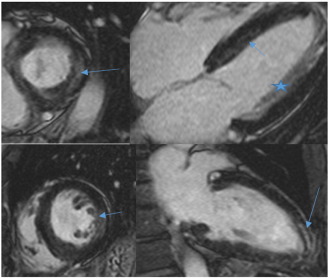

Fig. B.4.

CMR.

CMR short axis, 4-chamber and 2-chamber views in a 65-year-old female, 8 years post successful PBSCT of AL amyloidosis. CMR shows patchy mid-wall enhancement in a non-coronary distribution (arrows). Myocardial wall thickness is within the normal range, correlating with the echocardiogram findings of reduced myocardial thickness following treatment. Prominent papillary muscles are also seen laterally in the 4-chamber view (star), with associated blood pooling. The changes correspond to the patients clinical improvement.

Fig. B.5.

Cardiac MRI mid-ventricle short axis and 4-chamber views performed on a 58-year-old female, 19 years following treatment and clinical regression. MRI demonstrates myocardial wall thickness in the normal range and diffuse subendocardial enhancement of the left ventricle (thin arrows) and right ventricular aspect of the interventricular septum (broad arrow). The enhancement is in a non-coronary distribution which would support residual areas of amyloid protein deposition following treatment.

There was good correlation of the ejection fractions and left ventricular wall thicknesses between CMR and echocardiography (see Table A.2, Fig. B.4 ;  Fig. B.5). All four of the CMR studies suggested persisting presence of patchy diffuse gadolinium enhancement, consistent with the ongoing presence of residual insoluble amyloid material. In each case on CMR, there was diffuse myocardial enhancement of both ventricles with relative ventricular apical sparing, a pattern typical for amyloidosis infiltration [14] ;  [27]. The extent of enhancement in the majority of myocardial segments was subendocardial or involved the mid-wall with limited transmural enhancement (see Fig. B.4 ;  Fig. B.5). On average, 3.5/17 segments demonstrated transmural enhancement, predominantly within the left ventricular free wall (segments 5, 6, 11, and 12 of the 17-segment model). There was also patchy enhancement within the right ventricle in each case and minimal patchy enhancement in the atrial walls. Ventricular wall thickness was in the normal range or near normal in each case, and there was no significant interatrial septal thickening [28].

CMR had not been performed before PBSCT for these patients. Persistent reversal of the cardiac changes on echocardiography suggests significant regression of the infiltrative process in these patients. It was therefore surprising to see gadolinium uptake with CMR, indicating persistent amyloid infiltration of the myocardium. Myocardial enhancement in amyloidosis has been described as a very poor prognostic indicator, with pathophysiological studies suggesting that the enhancement is secondary to amyloid protein deposition in the extracellular matrix of the heart [16] ;  [28]. The pattern of enhancement following treatment with PBSCT remained typical for amyloid, with a subendocardial or mid-wall distribution. This CMR pattern has been associated with milder disease [14]. The enhancement pattern was not associated with myocardial thickening, which suggests reduced protein deposition and an associated decrease in myocardial oedema. Previous case reports and series have demonstrated a decrease in myocardial wall thickness and enhancement following PBSCT [19]; [20] ;  [21].